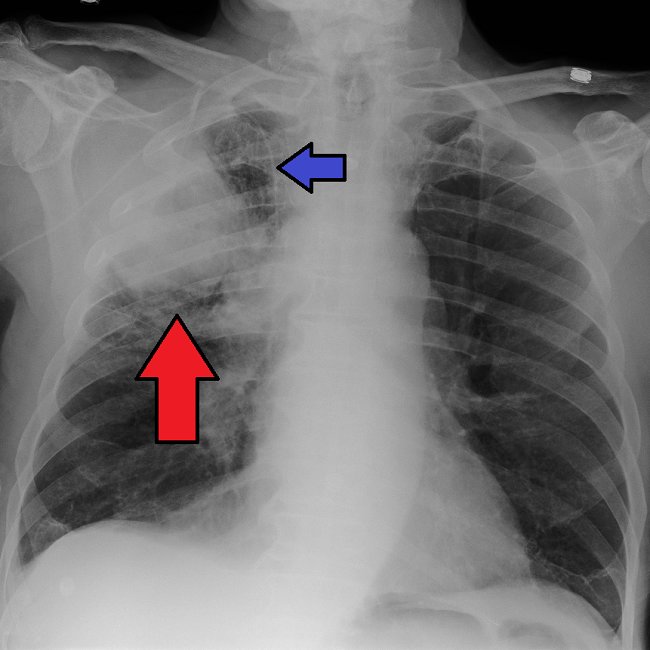

Beberapa prosedur diagnostik dapat dilakukan untuk menegakkan diagnosis kanker paru seperti rontgen toraks, CT scan, dan MRI pada toraks. Pemeriksaan histopatologi merupakan gold standar dalam menegakkan diagnosis kanker paru. Pengambilan sampel sel kanker pada pemeriksaan histopatologi dapat dilakukan dengan prosedur biopsi melalui bronkoskopi, biopsi transtorakal (TTB), serta torakoskopi.[1,3,6]